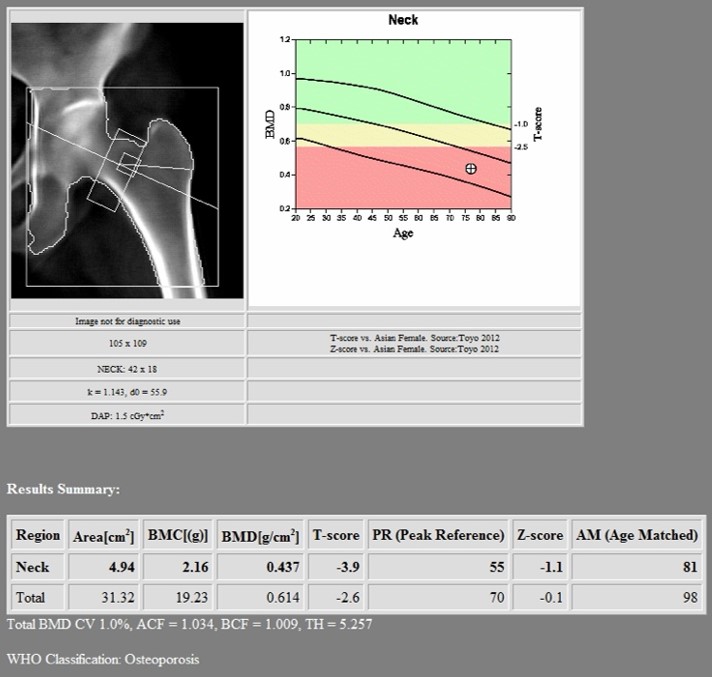

1st DXA Scan (Before Romosozumab treatment)

2nd DXA Scan (1 year after romosozumab treatment)

Hologic Horizon W

- LSC AP Spine 0.022 g/cm2

- LSC Neck of Femur 0.028 g/cm2

- LSC Total Hip 0.027 g/cm2

Changes in BMD after completing 1 year of Romosozumab

- Lumbar Spine = +0.121 g/cm2 (22.04%)

- Neck of Femur = +0.03 g/cm2 (6.86%)

- Total Hip = +0.049 g/cm2 (7.98%)

There was an increase in the BMD after she underwent 1 year of treatment with Romosozumab:

- Lumbar Spine: +0.121 g/cm2 (22.04%, LSC 0.022)

- Neck of Femur: +0.03 g/cm2 (6.86%, LSC 0.028)

- Total Hip: +0.049 g/cm2 (7.98%, LSC 0.027)

All the increases in these three parameters were higher than the respective LSC.

- DXA scan showed that the changes in BMD after completing 1 year of romosuzumab was: